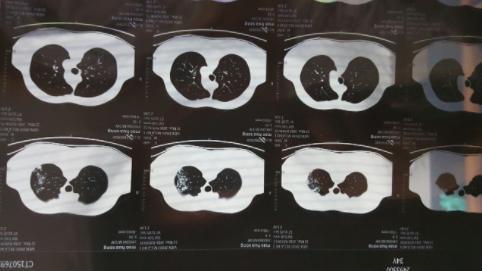

经过了疫情的一波冲击,大部分人都经历了一次新冠病毒的感染,阳康之后很多人都选择拍胸部CT查看自己的身体情况,当人们在看到自己的检查单上写着”肺部纤维灶“后吓了一跳,大部分人询问的问题都是”自己的肺部是不是纤维化了“、“肺部有玻璃阴影要紧吗”?

对于人们最关注的这些问题,上海市胸科医院呼吸与重症医学科副主任李峰表示,不必过度紧张,大部分人都只是出现了感染后的肺间质异常,本身是没有特别的其他症状,就像是一个伤痕,之后会慢慢恢复的,无需过多担心,李峰表示,当人在眼眶后检查胸部CT,的确会发现肺部会有一些磨玻璃影,磨玻璃小结节等情况,这都是由于感染病毒之后才出现的,一般情况下不会再扩大,而且过一段时间就会慢慢康复。

对于之前感染新冠病毒之后出现了肺部感染的人群建议等康复之后观察随访,等到三个月到6个月左右,复查CT,如果没有其他不适的症状,可以等到阳康之后3~6个月左右再检查胸部CT,李峰解释道,对于轻症的肺炎患者,做检查显示肺部有纤维条缩影的情况无需特殊的干预。

专家表示,正常情况下,肺部出现纤维灶并不代表一定是坏的,这就像是人身体某个部位被划伤之后留下的一个伤疤,不用特殊治疗,也不用吃药,肺纤维化分为两种,一种是指特发性肺纤维化,第2种是继发性纤维化,人们感染新冠后出现的属于继发性肺纤维化,重重就轻的,甚至充不上肺纤维化,所以无需过度担心。